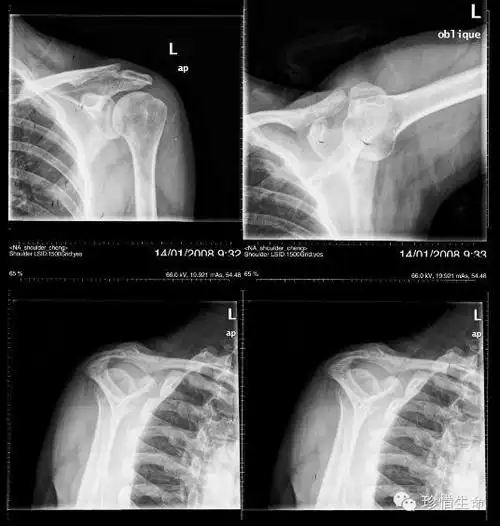

左肩锁关节脱位

肩关节的摄影体位

肩关节x线检查体位大全

术前x线片示弧形肩峰肩峰成形术后x线片所见总结,导致肩关节疼痛的

术后右肩关节正位片

一文了解肩部x线片拍摄方法